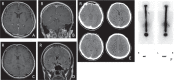

Spontaneous intracranial hypotension (SIH) has increasingly been recognized, and it is well known that SIH is sometimes complicated by chronic subdural hematoma (SDH). In this study, 55 cases of SIH with SDH were retrospectively analyzed, focusing on therapeutic strategies and outcomes. Of 169 SIH cases (75 males, 84 females), 55 (36 males, 19 females) were complicated by SDH. SIH was diagnosed based on clinical symptoms, neuroimaging, and/or low cerebrospinal fluid pressure. Presence of orthostatic headache and diffuse meningeal enhancement on magnetic resonance imaging were regarded as the most important criteria. Among 55 SIH with SDH cases, 13 improved with conservative treatment, 25 initially received an epidural blood patch (EBP), and 17 initially underwent irrigation of the hematomas. Of the 25 initially treated with EBP, 7 (28.0%) needed SDH surgery and 18 (72.0%) recovered fully without surgery. Of 17 SDH cases initially treated with surgery, 6 (35.7%) required no EBP therapy and the other 11 (64.3%) needed EBP and/or additional SDH operations. In the latter group, 2 cases had transient severe complications during and after the procedures. One of these 2 cases developed a hoarse voice complication. Despite this single, non-severe complication, all enrolled in this study achieved good outcomes. The present study suggests that patients initially receiving SDH surgery may need additional treatments and may occasionally have complications. If conservative treatment is insufficient, EBP should be performed prior to hematoma irrigation.